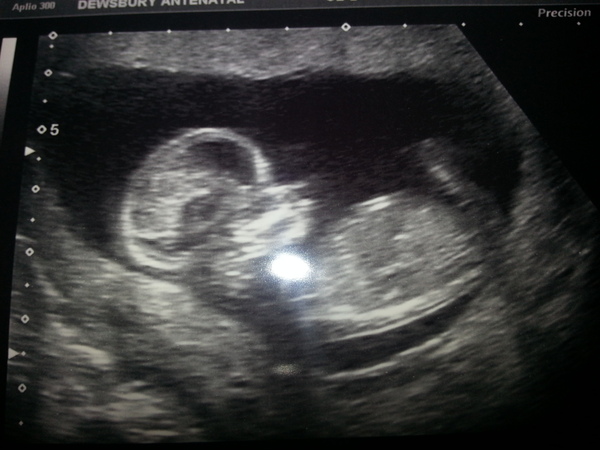

All went well at our scan today. Baby took a while to get in position and seems pretty chilled out in there. Baby Half gave us a wave though and I shed a tear. NT measurement seemed fine, so I think I will announce to the rest of the family that still don't know yet. Such a lovely feeling knowing that you are really pregnant and it is not all in your head. I only did one preg test, and this was the first scan so sigh of relief x

Due date moved forward 1 day so now due 4th Jan - but likely I will have a cs anyway, so baby half is likely to be an end of december baby x

12+5